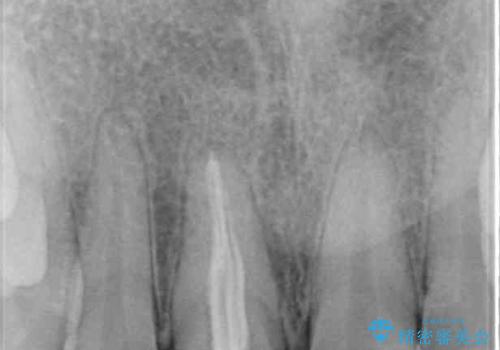

レントゲン写真より、歯根の炎症が認められなかったため、ファイバーコアによる土台築製後、オーダーメイドタイプのオールセラミッククラウンにて補綴することとしました。